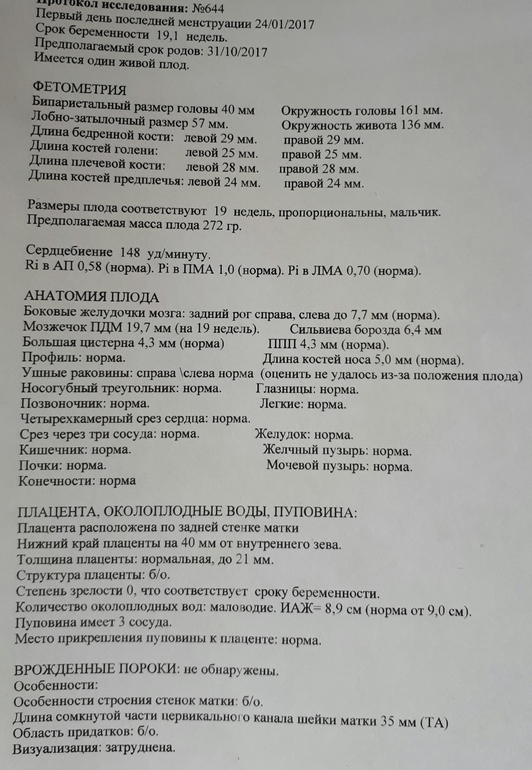

Сегодня начала проходить генетика и сделали второе скрининговое узи. Очень переживала за своего Никитку, что после всех препаратов в реанимации и после будет что-то не так. Слава Богу, всё хорошо. Только маловодие.